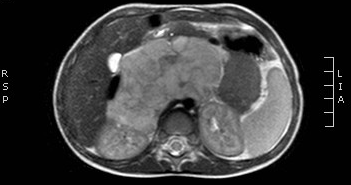

18. 5. Abdominal masses

Neuroblastoma. is a tumor that develops at any part of the sympathetic nervous system. Therefore, in over 90% of the cases the urinary catecholamine levels are elevated. It is the most frequent extra cranial, solid tumor in children and has its highest malignancy rate within the first year. It is most common in children aged 1-5 years, appears as a palpable abdominal mass, with fever, hypertension, and anemia; in cases of bone metastases, bone pain and limping are common. US examination reveals a well circumscribed, echogenic mass usually crossing the midline, dislocating the kidney; it is frequently calcified, highly vascular, surrounding and compressing the abdominal vessels. In progressive cases liver and nodal metastases can be found. The tumor can also be solid, homogenous and with a smooth margin. The adrenal region in newborns is well visualizeable with US, but at older ages only major lesions can be depicted. CT/MRI examination: can depict a large sized, irregular shaped, extrarenal mass, with frequent necrosis, hemorrhage and calcifications. The lesions show a heterogeneous contrast enhancement.

26. MRI examination, axial T2 weighted image. Irregular, large solid, inhomogeneous retroperitoneal tumor is seen. Neuroblastoma. (with the courtesy of Dr. Gábor Rudas)

Wilms tumor. It is the most common kidney tumor in childhood that appears between 2-5 years of age. It is usually only noted when the tumor is palpable as an abdominal mass. Hematuria, hypertension, vomiting and abdominal pain are also part of the clinical picture. US examination is a basic method in both the diagnostics and the follow-up of the tumor. The tumor is normally seen as a homogenous or an inhomogeneous mass, dislocating the pyelon and the surrounding retroperitoneal blood vessels. It is important to rule out any lesion in the other kidney. MRI examination: gives a picture of the entire abdomen, kidneys included. Nodal metastases, tumor thrombus are well depictable. CT-examination: is to be chosen if MRI is not available. The tumor shows an inhomogeneous contrast enhancement and pulmonary metastases (invisible to x-ray examination) are also depictable.

28. MRI examination axial, T2weighted sequence. A solid mass arising from the right kidney and filling out the right side of the abdomen, with peripheral follicular cystic components. Wilms tumor. (with the courtesy of Dr. Gábor Rudas)

29. CT-examination after iv. contrast administration. Mostly hypodense mass arising from the left kidney. Wilms tumor. (with the courtesy of Dr. Z. Karádi)